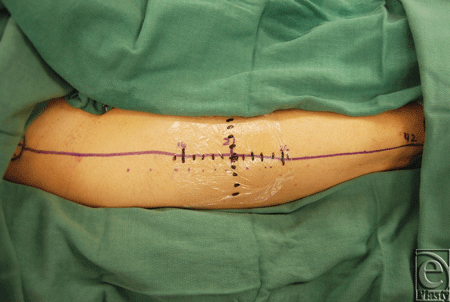

For each patient, a line was drawn from the anterior superior iliac spine to the lateral border of the patella and the laser was centered over the midpoint as previously described.5 An X-Y system of one-centimeter hatch marks, centered on the midpoint, was drawn onto the leg using a marking pen (Fig 1). Indocyanine green (12.5 mg) was injected intravenously and live fluorescence patterns were recorded using near-infrared laser angiography.

![]() |

| Figure 1. Donor leg displaying ABC perforator system with onlay XY grid. |